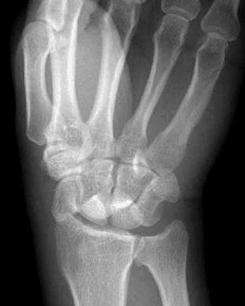

♥桡骨茎突骨折

桡骨茎突骨折多为跌倒时手掌着地,暴力沿腕舟骨冲击桡骨下端;或被翻转的摇手柄击伤桡骨茎突部所致的骨折,故也有摇手柄骨折之称,现在手摇柄汽车已罕见。骨折线常呈横形,波及桡腕关节,骨折块多无移位。[1]